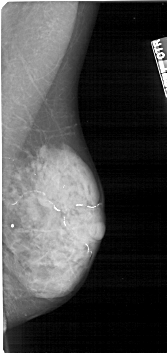

A_1223_1.LEFT_CC

LEFT_CC LINES 4921 PIXELS_PER_LINE 2551 BITS_PER_PIXEL 12 RESOLUTION 43.5 OVERLAY

FILE: A_1223_1.LEFT_CC.OVERLAY

TOTAL_ABNORMALITIES 1

ABNORMALITY 1

LESION_TYPE CALCIFICATION TYPE PLEOMORPHIC DISTRIBUTION CLUSTERED

ASSESSMENT 4

SUBTLETY 4

PATHOLOGY MALIGNANT

TOTAL_OUTLINES 1

BOUNDARY